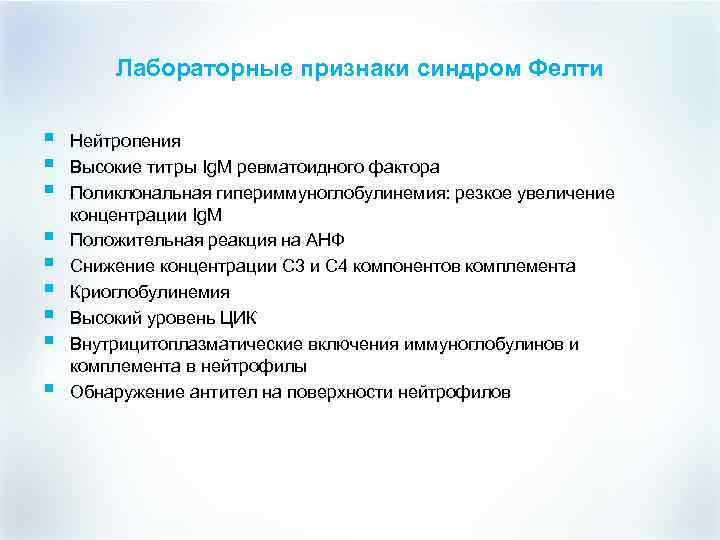

Лабораторные признаки синдром Фелти § § § § § Нейтропения Высокие титры Ig. M ревматоидного фактора Поликлональная гипериммуноглобулинемия: резкое увеличение концентрации Ig. M Положительная реакция на АНФ Снижение концентрации С 3 и С 4 компонентов комплемента Криоглобулинемия Высокий уровень ЦИК Внутрицитоплазматические включения иммуноглобулинов и комплемента в нейтрофилы Обнаружение антител на поверхности нейтрофилов

Лабораторные признаки синдром Фелти § § § § § Нейтропения Высокие титры Ig. M ревматоидного фактора Поликлональная гипериммуноглобулинемия: резкое увеличение концентрации Ig. M Положительная реакция на АНФ Снижение концентрации С 3 и С 4 компонентов комплемента Криоглобулинемия Высокий уровень ЦИК Внутрицитоплазматические включения иммуноглобулинов и комплемента в нейтрофилы Обнаружение антител на поверхности нейтрофилов